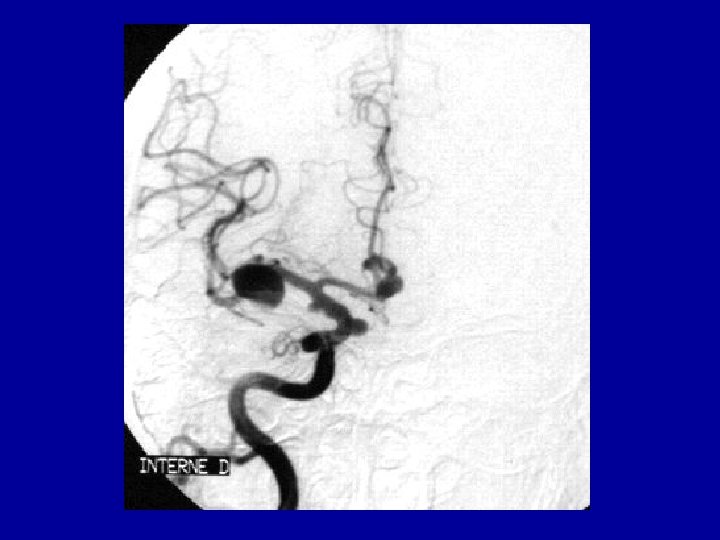

• Artériographie cérébrale • Explore les 4 axes (2 carotides, 2 vertèbrales) • Démontrer l'existence d’un anévrysme • Localisation • Mode d’implantation • Nombre